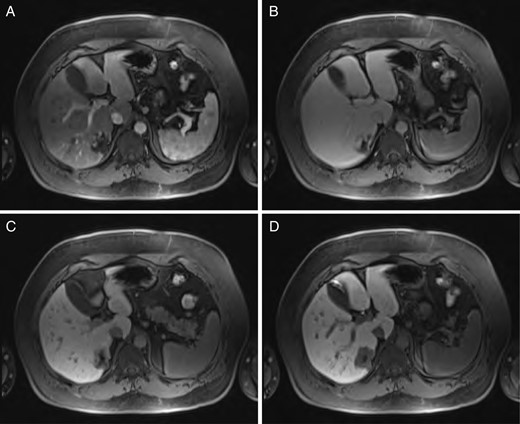

A 40-year-old male underwent computed tomography (CT) scan of the chest for atypical chest pain, which revealed an indeterminate 3-cm lesion in the right liver. He subsequently underwent triple-phase CT, which revealed two separate lesions: a 4.3 × 5.3-cm discrete mass in the left liver (Segment 2) and a 2.3 × 3.7-cm lobular, partially exophytic hypodense lesion in the right liver (Segment 6). On the delayed phase, the periphery of the right posterior hepatic mass was isodense with the rest of the liver parenchyma, but the central portion remained hypodense. Based on these findings, the right-sided lesion was felt to be a hemangioma, but the findings were still inconclusive regarding the left-sided lesion. Magnetic resonance imaging (MRI) was performed with intravenous gadoxetic acid, a hepatocyte-specific contrast agent. The lesion in Segment 2 was hypointense on precontrast T1, hyperintense on T2-weighted images, and showed avid enhancement on the arterial and portal venous phases. There was a delayed washout on the hepatographic phase. Although nonspecific, this was felt to be most consistent with an adenoma. The right-sided lesion showed postcontrast gradual enhancement with centripetal fill-in, reinforcing the diagnosis of hemangioma (Figs 1 and 2).

Sequential MRI imaging of hepatic hemangioma. Note delayed centripetal filling: (A) T1 arterial phase, (B) T1 60-s delay phase, (C) T1 postcontrast phase and (D) T1 hepatographic phase.